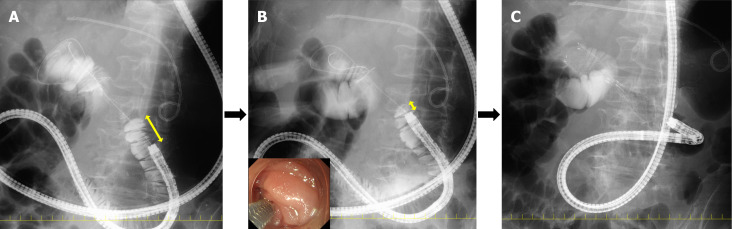

十二指肠支架置入术是一种广泛应用于胃出口梗阻(GOO)的姑息性治疗方法,由不可切除的恶性肿瘤引起。与外科胃空肠造口术相比,十二指肠支架植入术允许更早的口服摄入,更短的住院时间和更早的化疗开始。然而,其长期疗效受到支架阻塞的限制,支架阻塞通常发生在手术后2-4个月,原因是肿瘤向内生长、过度生长或食物嵌塞。覆盖支架可以减少肿瘤向内生长,但增加了肿瘤迁移的风险,特别是在接受化疗的患者中。本文综述了十二指肠支架置入术、外科胃空肠造口术和超声内镜引导下的胃肠造口术的临床结果、优点和局限性。我们进一步探讨基于狭窄特征的支架选择、最佳放置技术、术后处理以及包括闭塞、迁移、出血和穿孔在内的并发症的处理。此外,我们还讨论了技术挑战和故障排除策略,包括在胆道和十二指肠重叠狭窄病例中导丝诱导穿孔、支架扩张不完全和胆管阻塞的处理。尽管其广泛的临床应用,但没有先前的综述全面地涵盖了十二指肠支架置入术的技术和临床方面。通过提供临床导向的实用指南,本综述为内窥镜医师和胃肠病学家提供了宝贵的资源,有助于优化决策并改善GOO患者在实际实践中的预后。

Duodenal stenting is a widely used palliative treatment for gastric outlet obstruction (GOO) caused by unresectable malignancies. Compared to surgical gastrojejunostomy, duodenal stenting allows for earlier oral intake, shorter hospitalization, and earlier chemotherapy initiation. However, its long-term efficacy is limited by stent occlusion, which typically occurs 2-4 months post-procedure, due to tumor ingrowth, overgrowth, or food impaction. Covered stents can reduce tumor ingrowth but increase the migration risk, particularly in patients receiving chemotherapy. This review provides a comprehensive comparison of duodenal stenting, surgical gastrojejunostomy, and endoscopic ultrasound-guided gastroenterostomy, by discussing their clinical outcomes, advantages, and limitations. We further explore stent selection based on stricture characteristics, optimal placement techniques, post-procedural management, and for handling complications including occlusion, migration, bleeding, and perforation. Additionally, we address technical challenges and troubleshooting strategies, including management of guidewire-induced perforation, incomplete stent expansion, and bile duct obstruction for overlapping biliary and duodenal stricture cases. Despite its widespread clinical use, no prior review has comprehensively covered both the technical and clinical aspects of duodenal stenting so extensively. By providing a clinically oriented, practical guide, this review serves as a valuable resource for endoscopists and gastroenterologists, facilitating optimized decision-making and improved outcomes for patients with GOO in real-world practice.